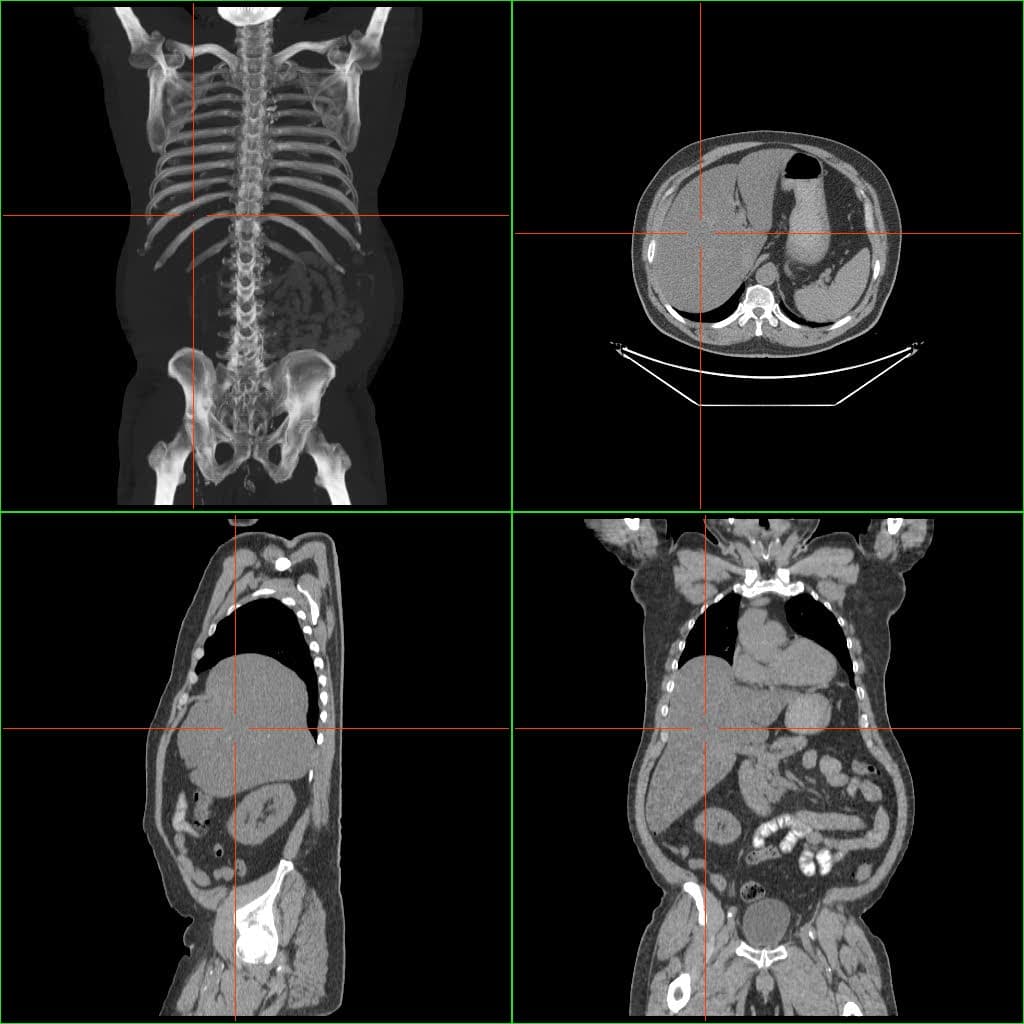

Hepatomegaly is enlargement of the liver. It is a non-specific medical sign, having many causes, which can broadly be broken down into infection, hepatic tumours, and metabolic disorder. Often, hepatomegaly presents as an abdominal mass. Depending on the cause, it may sometimes present along with jaundice. The patient may experience many symptoms, including weight loss, poor appetite, and lethargy; jaundice and bruising may also be present. Among the causes of hepatomegaly are the following: The mechanism of hepatomegaly consists of vascular swelling, inflammation (infectious in origin), and deposition of (1) non-hepatic cells or (2) increased cell contents (such as that due to iron in hemochromatosis or hemosiderosis and fat in fatty liver disease). Suspicion of hepatomegaly indicates a thorough medical history and physical examination, wherein the latter typically includes an increased liver span. On abdominal ultrasonography, the liver can be measured by the maximum dimension on a sagittal plane view through the midclavicular line, which is normally up to 18 cm in adults. It is also possible to measure the cranio-caudal dimension, which is normally up to 15 cm in adults. This can be measured together with the ventro-dorsal dimension (or depth), which is normally up to 13 cm. Also, the caudate lobe is enlarged in many diseases. In the axial plane, the caudate lobe should normally have a cross-section of less than 0.55 of the rest of the liver. Other ultrasound studies have suggested hepatomegaly as being defined as a longitudinal axis > 15.5 cm at the hepatic midline, or > 16.0 cm at the midclavicular line. Blood tests should be done, especially liver-function tests, which give a good impression of the patient's broad metabolic picture. A complete blood test can help distinguish intrinsic liver disease from extrahepatic bile-duct obstruction. An ultrasound of the liver can reliably detect a dilated biliary-duct system, it can also detect the characteristics of a cirrhotic liver.